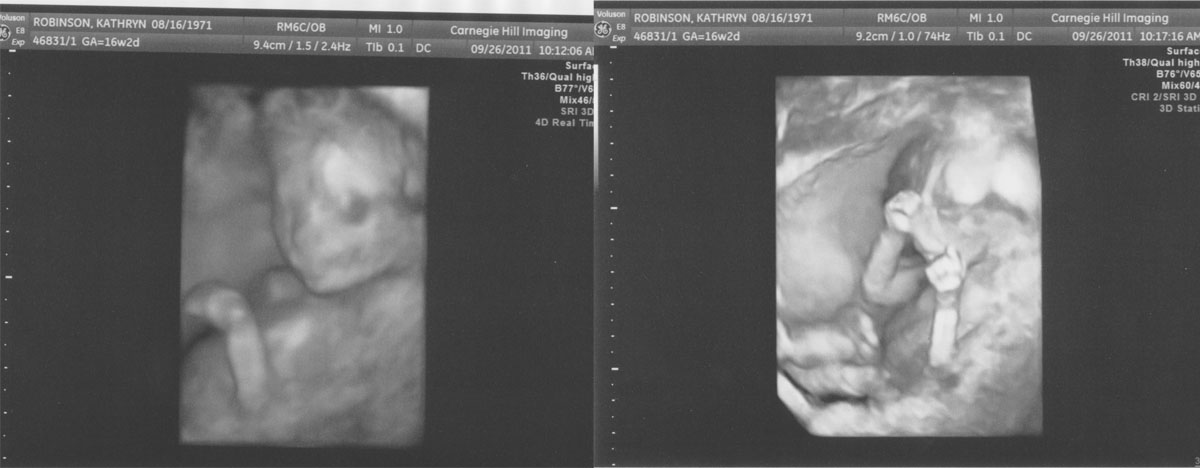

16 Weeks (3D Imaging!)